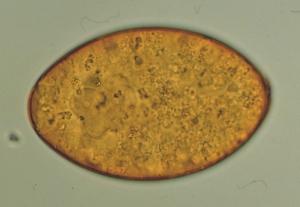

9- Grande Douve du Foie : Fasciola hepatica

Photo Laboratoire Mérial

Morphologie : Trématode hermaphrodite, ver plat asegmenté, mesurant 20-30 mm de long pour 10 de large, avec un cône cépahlique antérieur et des élargissement scapulaires marqués. Présence à l'état frais de bandes brunes latérales correspondant aux glandes vitellogènes.

Œufs : Grande taille 120-140 x 80 µm, ovalaire, à coque mince, operculée, renfermant un syncitium vitellin jaunâtre et un embryon (contenu granuleux jaunâtre).

Localisation : Parasite des canaux bilaires.

Epidémiologie : Infestation des chevaux sur des pâturages humides avec végétaux susceptibles d'avoir des métacercaires. Bien souvent en zone d'endémie de fasciolose des ruminants (bovins et ovins). Cycle identique à celui observé chez les ruminants, mais avec un taux de réussite plus faible. Prolificité inférieure des douves.

Etude clinique : Anémie, ictère, coliques.